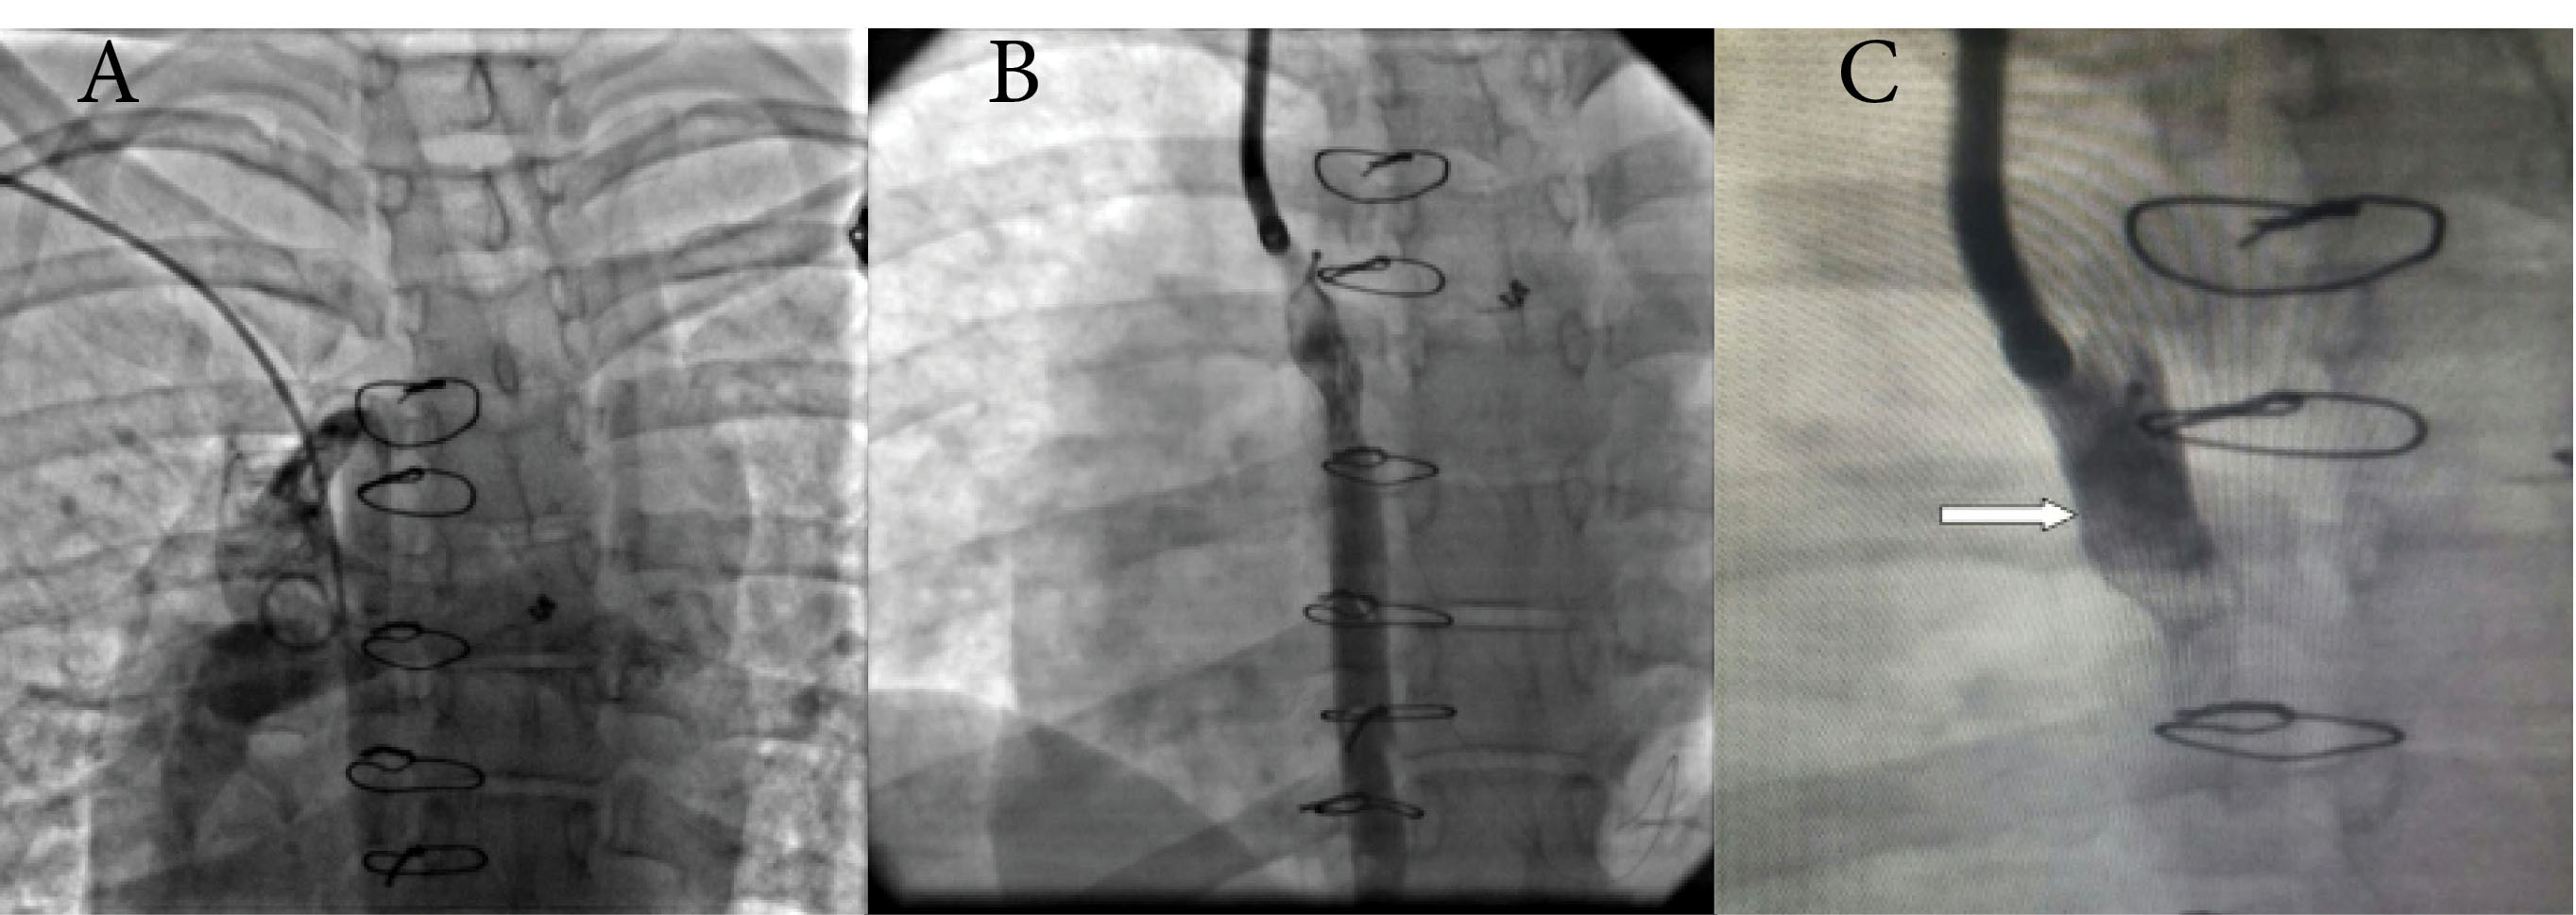

Figure 1.

(A) SVC angiography showed a large azygos vein in frontal projection and no other pulmonary venous fistula, (B) selective azygos angiogram was taken during VSD device occlusion, (C) Azygos injection after the whole occlusion procedure, the arrow shows VSD occluder device in proper position